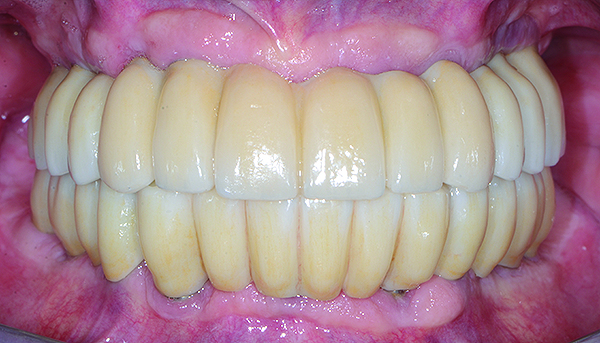

The maxillary prototype was adjusted, polished, and left to function with the mandibular provisional. The definitive maxillary zirconia restoration was then completed from the information provided by the prototype, and the cutbacks for the facial porcelain (Nos. 6 through 11) were done after milling but before sintering. Subsequently, the mandibular prototype was adjusted to the sintered and colored maxillary zirconia framework before the application of porcelain to Nos. 6 through 11 and final glazing (Figure 11). Following this step, the mandibular definitive monolithic zirconia restoration was milled, colored, and sintered. The facial porcelain (Nos. 6 through 11) was applied, and then both maxillary and mandibular restorations were stained and glazed (Figure 12). Both bridges were inserted at the same time (Figure 13 through Figure 15). Minor occlusal adjustments and oral hygiene access was verified and the zirconia surfaces polished. The bridge screws were torqued to 20 Ncm according to the manufacturer’s recommendation, and No. 24 was luted with a provisional cement. Postoperative radiographs were taken (Figure 16).

Fig 11. Intraoral frontal view of the maxillary zirconia restoration and adjusted mandibular PMMA prototype.

Figure 11

Fig 12. Extraoral frontal view of the completed maxillary and mandibular articulated zirconia restorations on master casts.

Figure 12